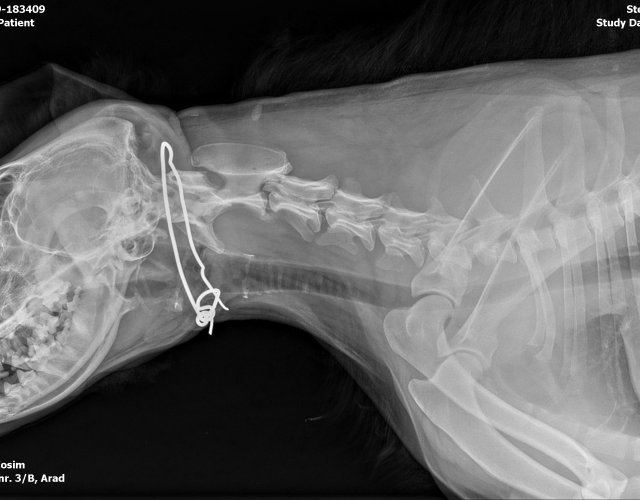

Caine accidentat

Asistență medicală -

O doamna a gasit un caine lovit de masina si l-a tras pe marginea drumului pentru a suna peste tot in cautare de ajutor. Am raspuns pozitiv si am facut totul pentru el. Din pacate nu a putut fi …